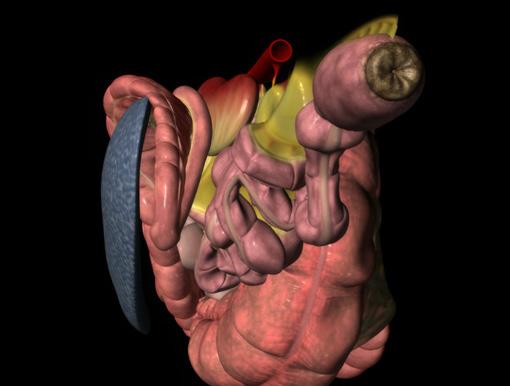

76 Reduce recurring entrapment colic

Jackie Bellamy-Zions talks to Dr. Nicola Cribb about new research showing how preventative surgery can reduce the risk of recurrent nephrosplenic entrapment colic in horses.